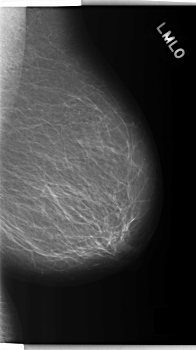

C_0276_1.LEFT_MLO

LEFT_MLO LINES 5944 PIXELS_PER_LINE 3328 BITS_PER_PIXEL 12 RESOLUTION 50 NON_OVERLAY